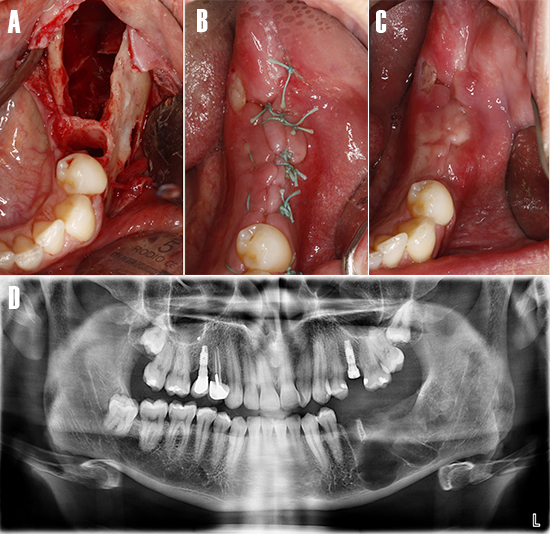

Una vez realizada la extracción de los dientes impactados, se legró la cavidad quística irrigando con abundante solución salina estéril, luego se realizó el cierre del colgajo (Fig. 8). El tejido inflamatorio extraído fue remitido a patología para el análisis histopatológico respectivo.

Figura 8. Extracción de los dientes impactados. Imagen intraoral - vista oclusal. A) Cavidad osteolítica tras la enucleación de la patología y extracción de los dientes impactados . B) Se realiza la sutura con puntos interrumpidos y seda no reabsorbible. C) Cicatrización a la semana postoperatoria. D) Ortopantomografía postoperatoria inmediata.